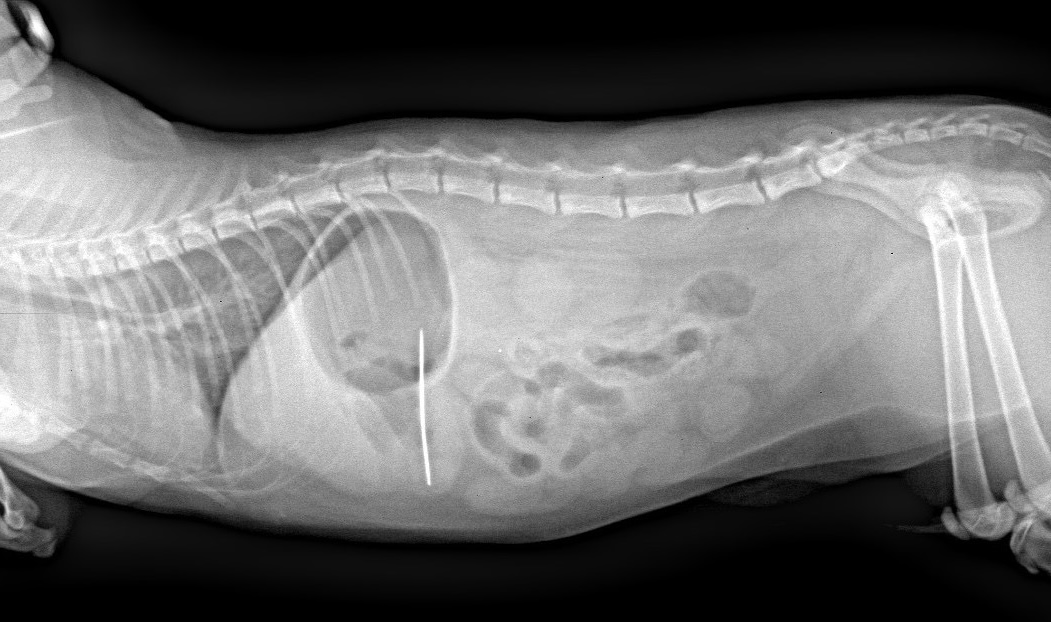

Якщо котик проковтнув голку з ниткою

Негайно зверніться до ветеринарного лікаря. Тваринку переміщуйте обережно, без стискань та різких рухів. Не задавайте ніяких ліків, воду і їжу також не давайте. Голка може пройти наскрізь стінку стравоходу, шлунку чи кишківника та викликати запалення в порожнинах тіла та інші ускладнення. Нитка може затягнутися та прорізати стінку кишківника, стягнути кишківник, викликати інвагінацію, непрохідність або розрив стінки. Неможна розраховувати, що голка з ниткою вийдуть самостійно. Треба без очікувань звернутися до ветеринарного спеціаліста.